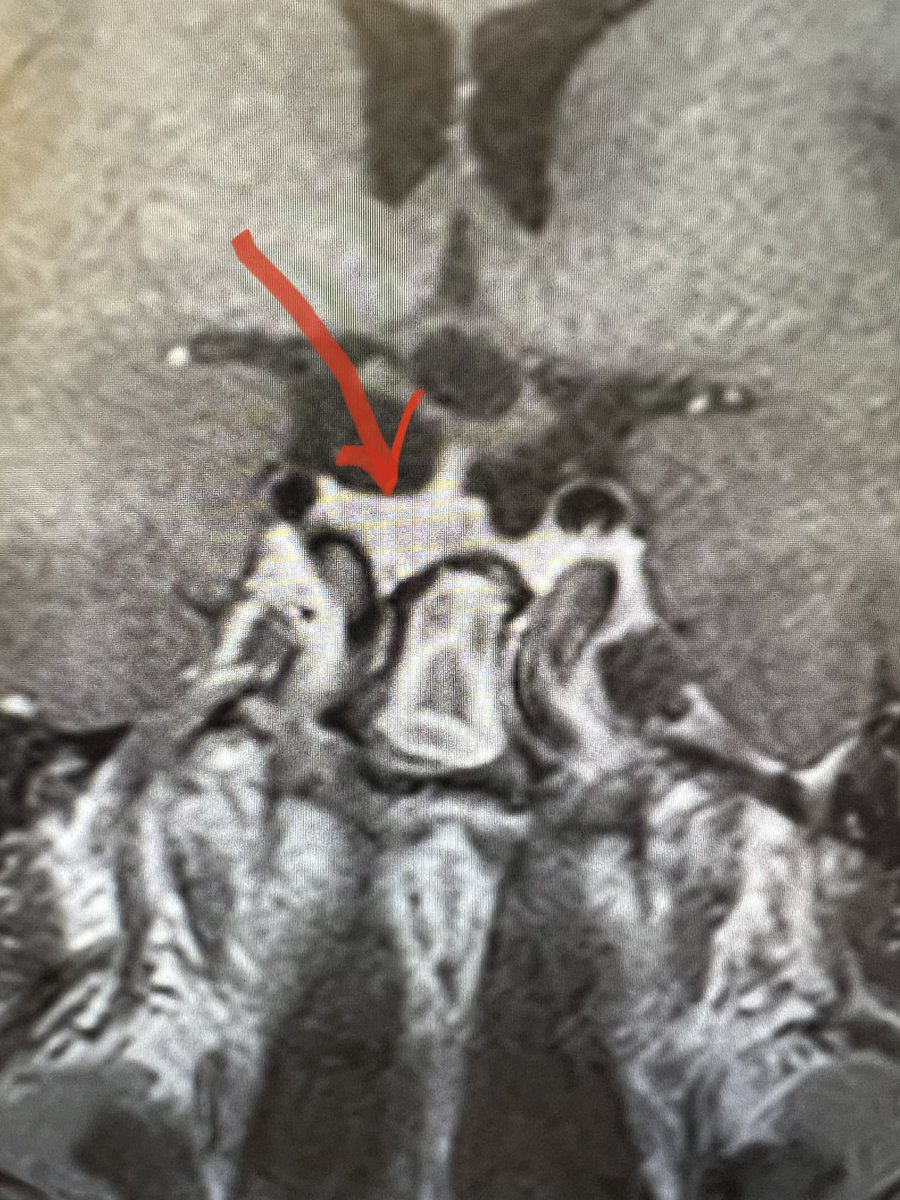

Just sharing the link to my case submission on MACS that is now available on the Cushing’s Hub website as an interactive case study. cushingshub.com/case-studies/a… @springermeded #Endotwitter